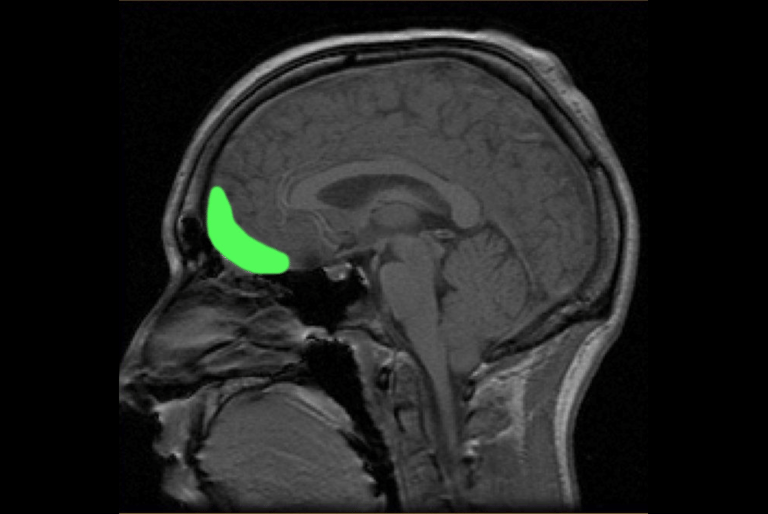

在三個不同的研究中,腦掃描器裡的受試者交替給某個東西的美(好比說臉)或某個行為的善做出評分。這兩類評價都活化了同一個區域——眼窩額葉皮質(orbitofrontal cortex,OFC),越是美或善,眼窩額葉皮質就越活化(而腦島就越不活化)。

文章插圖

圖中綠色處,為眼窩額葉皮質的所在位置。